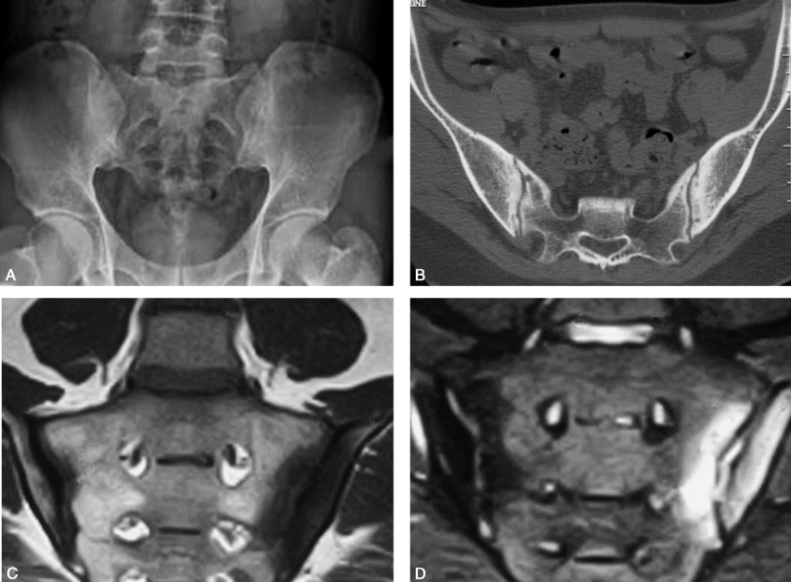

图1 强直性脊柱炎骶髂关节炎男,25岁。

A. 骨盆平片,骶髂关节骨性关节面粗糙不整呈锯齿状,以髂骨侧侵蚀为明显,关节间隙可呈假性增宽;

B. 骶髂关节CT横轴位显示更加清晰,关节面受侵蚀,局部囊变,以髂骨侧明显;

C. D. MR冠状位T1WI及T2WI,双侧骶髂关节病变呈长T1长T2信号。

X线上一般采用骶髂关节俯卧正位片,辅加斜位显示最佳。病变一般自下2/3髂侧关节面开始,双侧对称受累。AS既累及骶髂关节的滑膜部分又累及韧带,早期关节邻近骨质疏松,骨性关节面粗糙不整可呈锯齿状,常以髂骨侧侵蚀为明显,关节间隙可呈假性增宽。随病程进展,病变中期表现关节软骨破坏,关节间隙宽窄不一,关节面不规则,呈毛刷或锯齿状及囊变,继而出现反应性骨质硬化,关节不规则狭窄及纤维性或部分骨性强直(图1)。病变晚期关节间隙变窄并有骨小梁通过,最后发生骨性强直,骨密度逐渐恢复正常或保持疏松。

CT能清晰显示骶髂关节间隙,对于测定关节间隙有无增宽、狭窄、强直或部分强直有独到之处。CT检查可完全避免骶髂关节和脊椎的前后重叠,清楚地显示X线平片可疑的早期病变、脊柱骨折等。尤其对骶髂关节炎的诊断最敏感,能准确判定关节间隙的宽窄、骨皮质的中断、软骨下侵蚀和囊变等。在早期骶髂关节改变,CT对诊断骶髂关节炎早期表现的重要征象是关节面的侵蚀,破坏周围的多形性软骨下骨硬化和关节内的缺损均能清除显示(图1)。

MRI检查对AS早期诊断较X线平片和CT显示更为准确,能显示关节滑膜增厚和关节积液。关节积液呈长T1长T2信号,增强扫描滑膜强化;关节软骨水肿,当软骨炎性水肿,关节面下周围骨髓呈长T1长T2信号,此为早期改变(图1)。当异常纤维组织取代了正常髓核,髓核在T2WI上信号降低,而邻近椎体边缘破坏区内的信号强度增加,椎间隙变狭窄。与结核和化脓性骨髓炎不同,本病脊椎周围软组织形态和信号强度通常无变化。